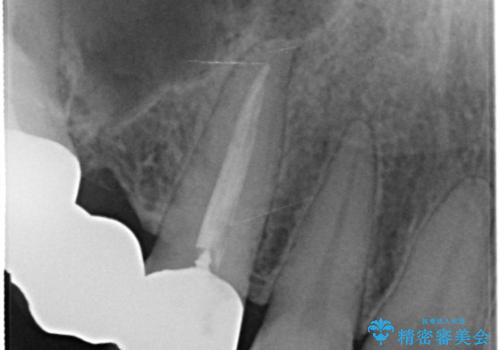

- 全体的な治療と、見た目をきれいにしたとのご希望で来院されました。

上顎の前歯はガタガタがあり、過去に治療した歯はつぎはぎのようになっており、審美的に周囲と調和がとれていない状態でした。

セラミックのかぶせ物だけで、歯並びまで変えようとするのには限界があります。

今回矯正治療で歯並びを整えた後に、セラミックを装着することにより、審美的・機能的に優れた仕上がりにすることができました。